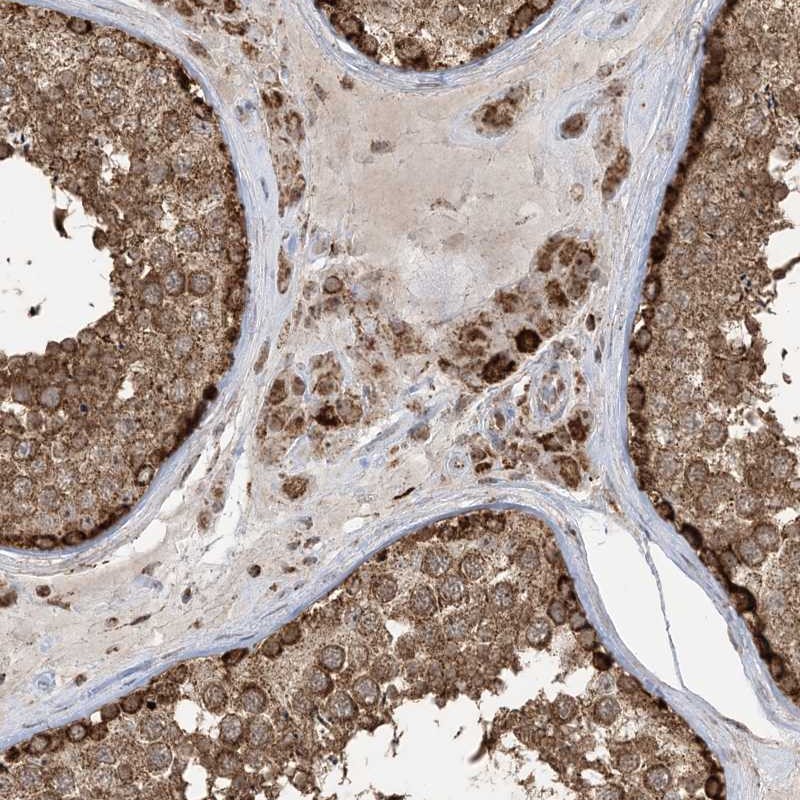

Immunohistochemistry analysis in human testis and pancreas tissues using Anti-MAPKBP1 antibody. Corresponding MAPKBP1 RNA-seq data are presented for the same tissues.